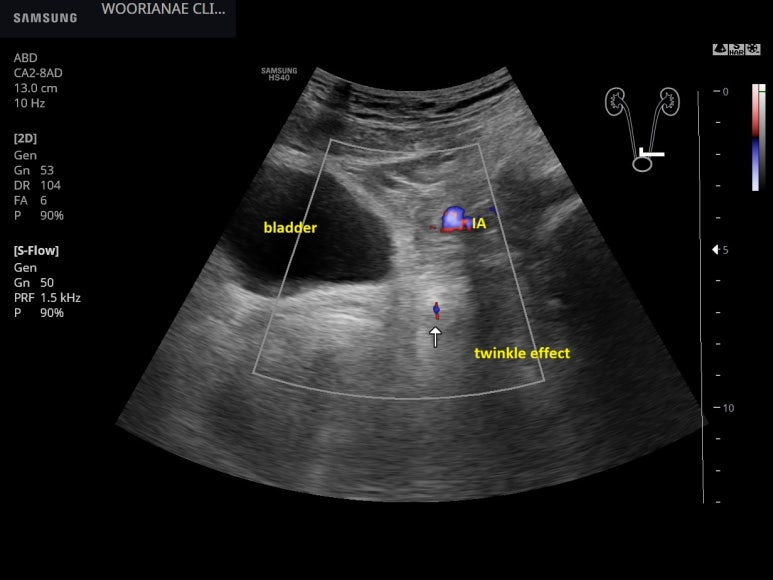

육안적 혈뇨, 과거와 같은 통증이 아니라 요로결석이라고 생각하지 않으며 방문, 수신증/요로 확장이 없는 방광요도이행부 결석 - 동대문구 답십리, 전농동, 우리안애 우리안愛 내과

50대 중반 남자 23년 말 검진, 당시 ALT 61로 초음파 상의하였으나... 응하지 않음. 음주는 하지 않음. 체질량 지수 28로 비만 ... 25년도 방문시 다른 의원에서 혈압약 투약한지 한달째 7월에 한번 처방 ... 6개월 만에 방문, 타의원에서 혈압약 유지중 이번 방문 이유는 혈뇨 커피색 오줌이다가 아침에 빨간 오줌이?? 3일째.. 낮에는 괜찮고.. 이전에 얘기하지 않았던 과거력. 과거 (24, 25년) 에 결석 3회 정도.. 쇄석술 2회, 한번은 저절로 빠진듯? 호전 "AI가 잘 되어있어 검색해보았는데 사구체 신염이 아닐지..." 가족도 진료를 보냈다는데... 아래가 부인이었다. 오래전에 대장내시경... 50대 중반, 진행성.. : 네이버블로그 복통이 뚜렷하지 않아 요로결석이라고 할 수 없으나 과거력이 있기도 하고 증상이 전형적이지 않은 경우도 있어 결석을 생각하고 초음파를 보자고 함 본인은 과거와 같이 아프지 않으니 결석에